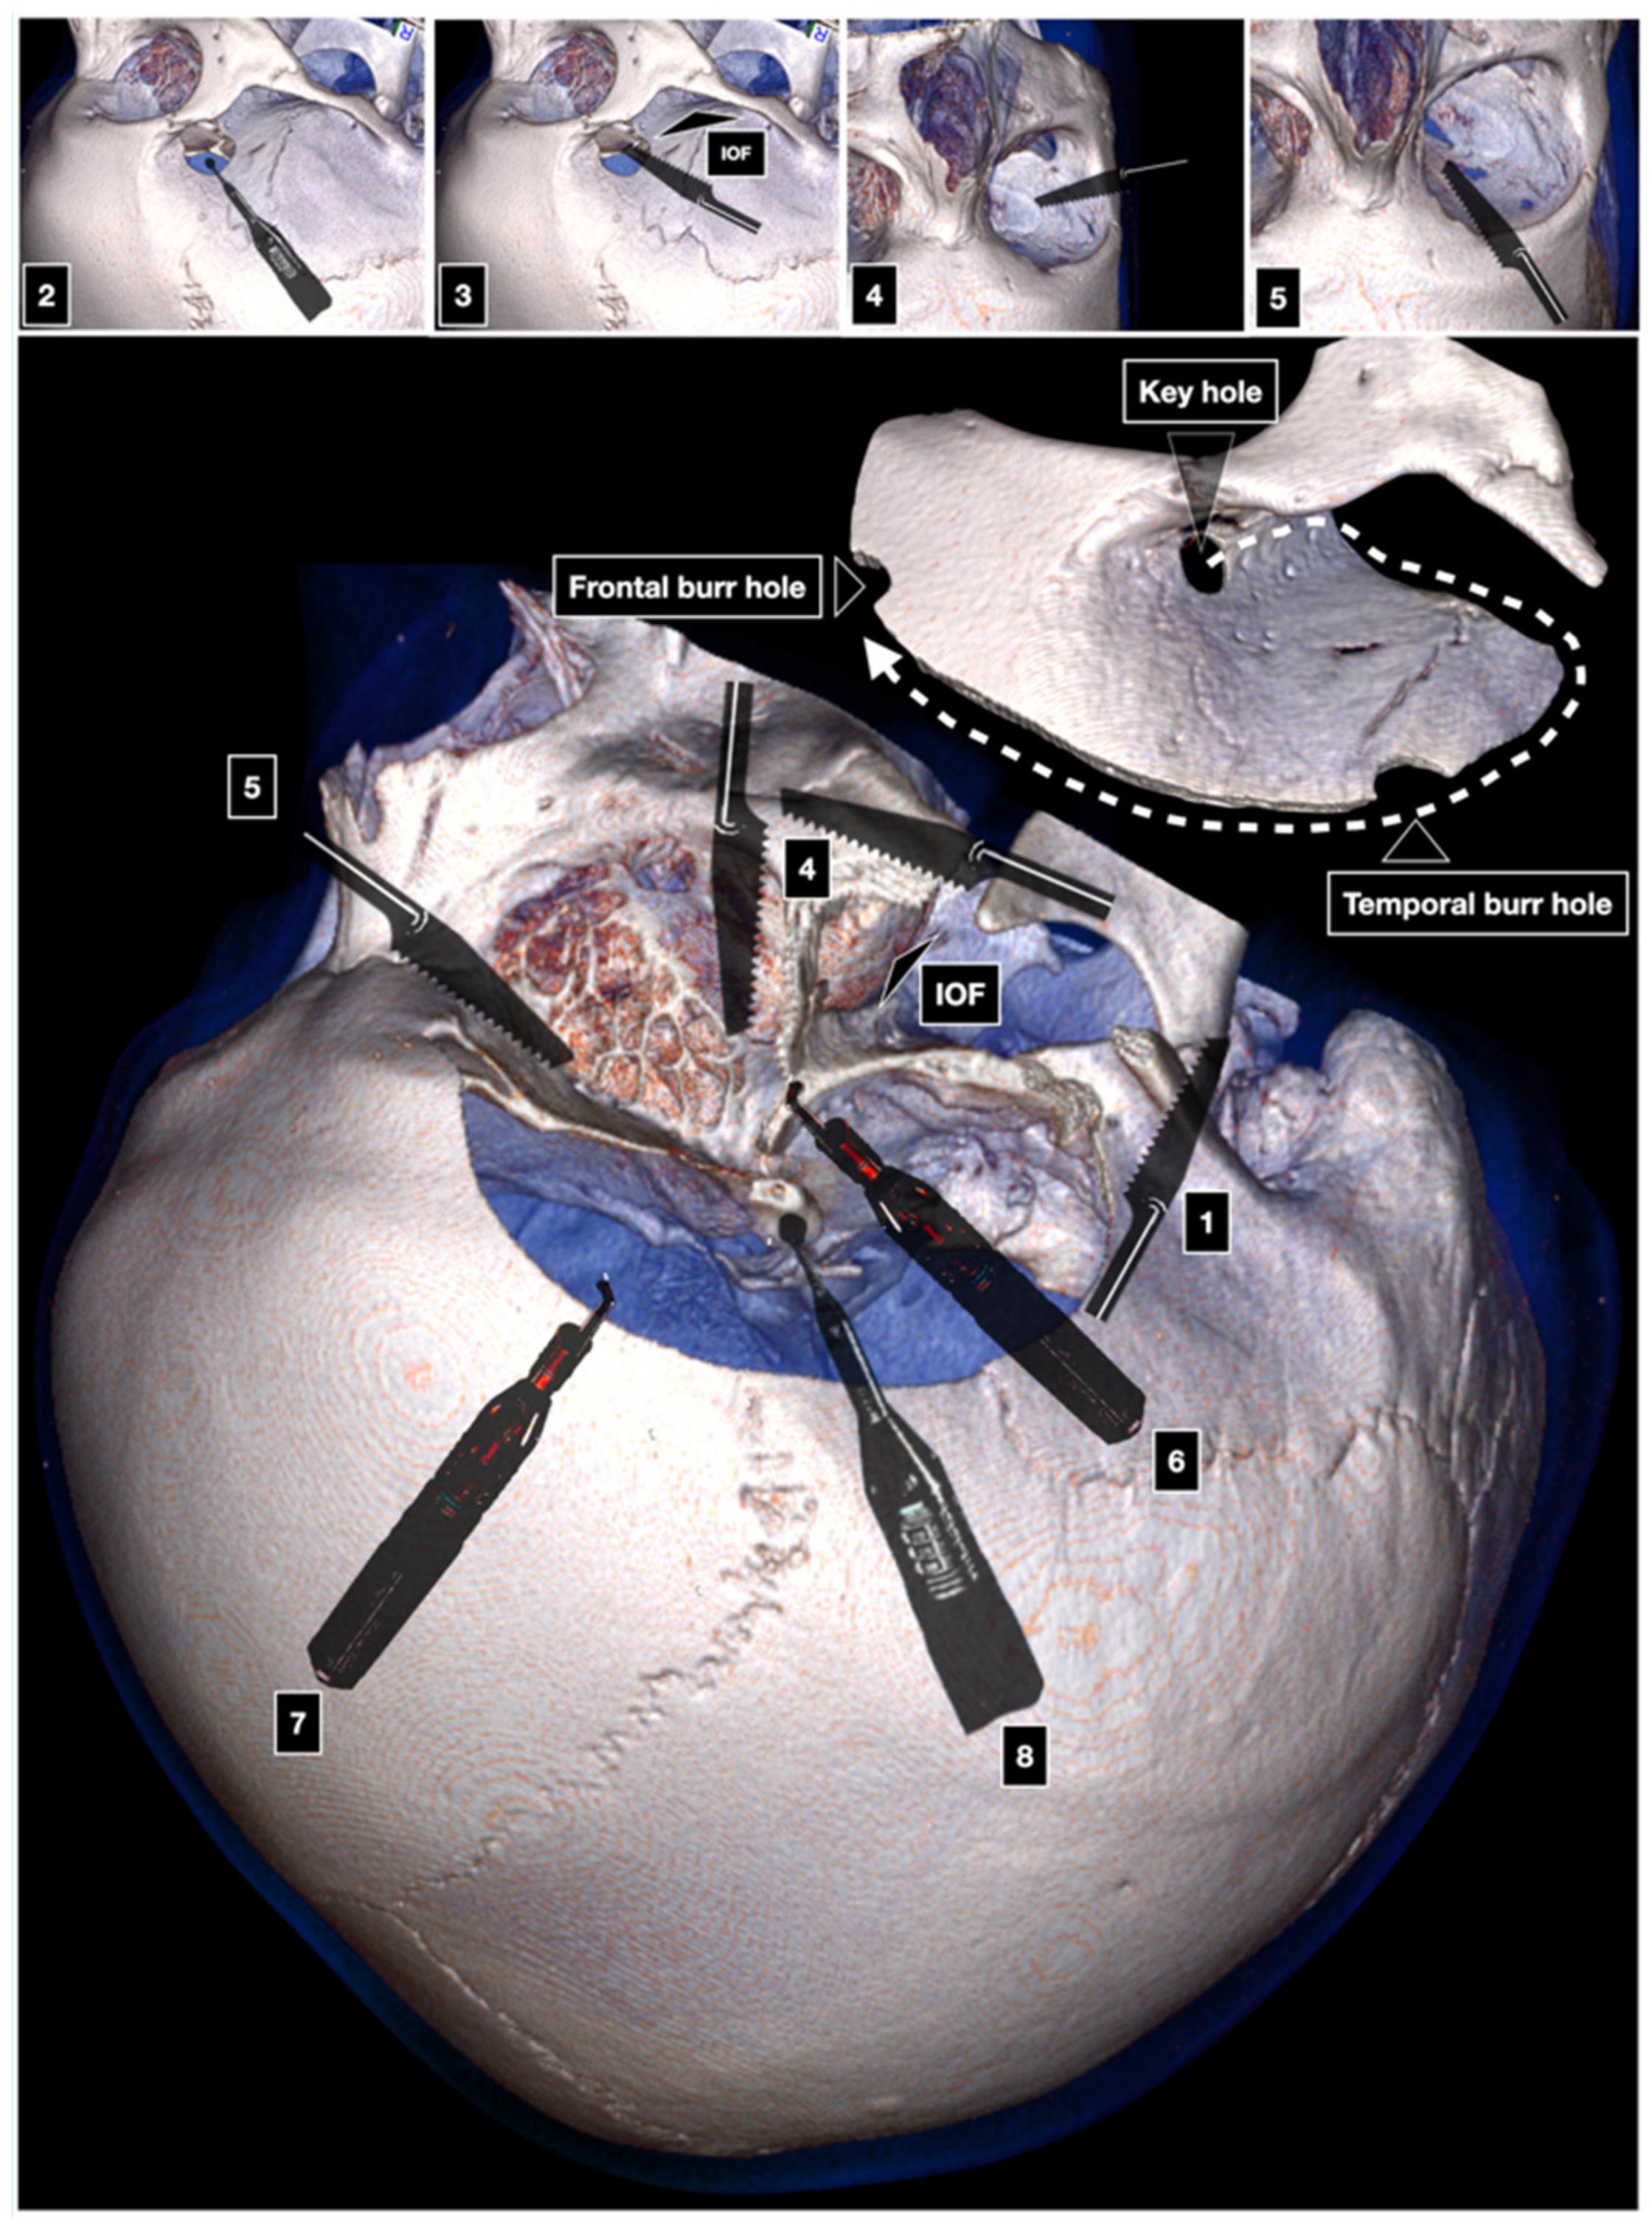

One-Piece Orbitozygomatic Craniotomy